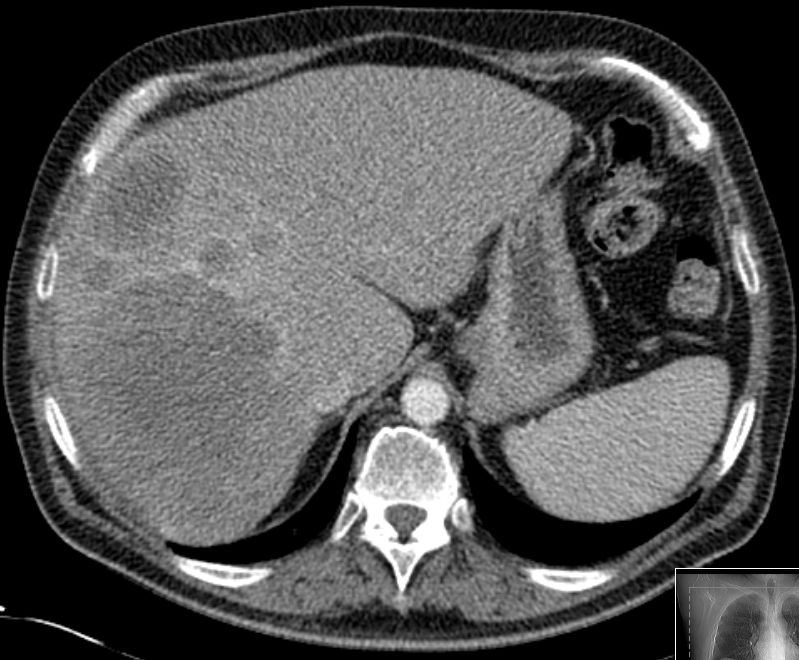

| Diagnostik | 67-jähriger Patient, der vor 3 Jahren ein Rektum-Ca im Stadium cT3 cN1 cM0 hatte. Vor 2 Jahre unklarer Leberherd, der jetzt an Größe zugenommen hat. Nach Resektion der Lebersegmente V und VI ergab sich ein cholangiozelluläres Karzinom pT1 G1. 05/16 CT ohne KM : V.a. HEP ![]() |